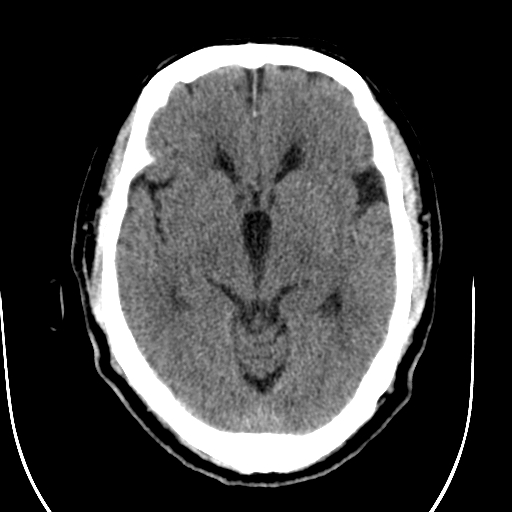

标题: CT28335:男,58岁,请各位看看是不是有脑积水,蝶窦内高密 [打印本页]

标题: CT28335:男,58岁,请各位看看是不是有脑积水,蝶窦内高密

轻度积水,蝶窦正常。

脑积水!建议行mri!

1)脑积水。2)副鼻窦炎。